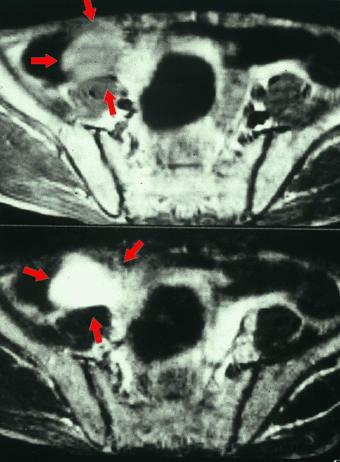

질환(병리주체)의 분류 기타 종양/악성 충수점액괴종

부위(장기별) 대장/충수

검사방법 MRI

종양의 최대경(밀리미터) 40이상